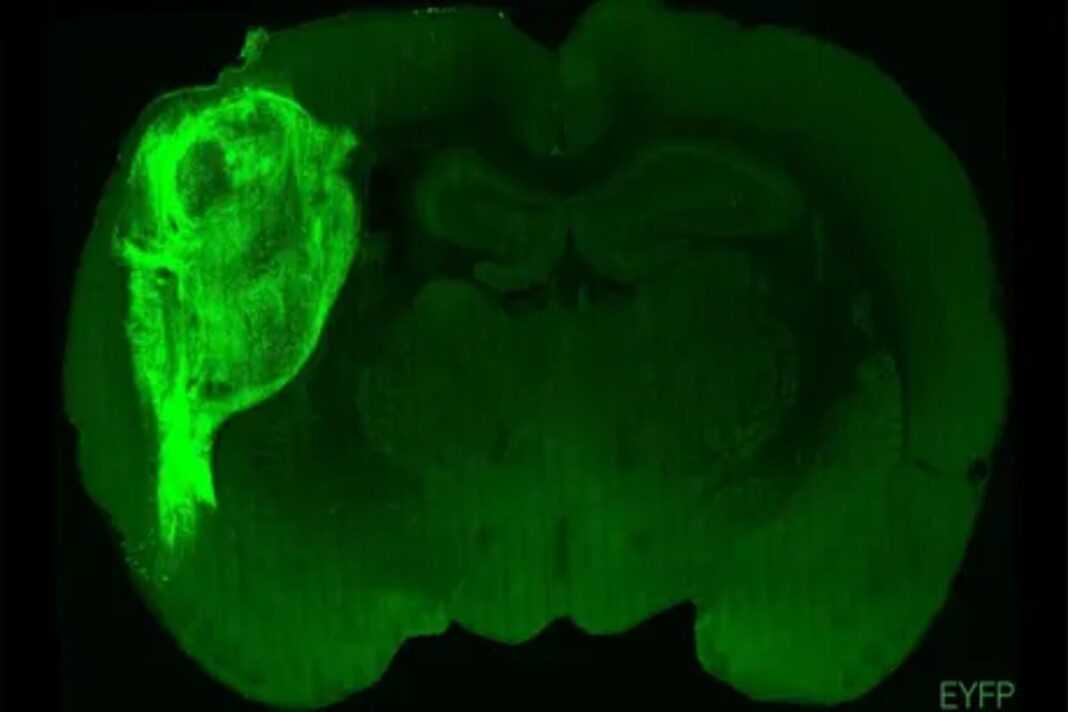

Ο εγκέφαλος είναι το πιο περίπλοκο και σημαντικό όργανο του σώματος – και πιθανότατα το πιο ευαίσθητο στις περιβαλλοντικές τοξίνες, αλλά ήταν σε μεγάλο βαθμό απρόσιτος στους ερευνητές έως ότου αναπτύχθηκαν εξελιγμένες τεχνικές απεικόνισης, γενετικές και μοριακές τεχνικές τα τελευταία 20 χρόνια.